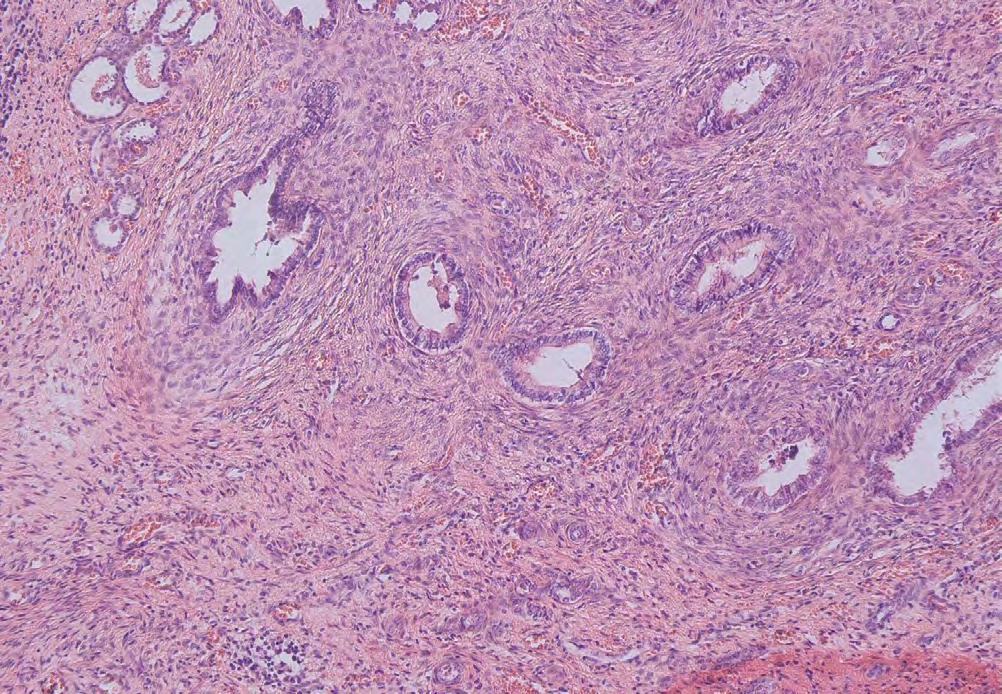

Histologické nálezy u kompletně zdvojené ledviny

164 a močovodu po heminefrektomii

Histological findings in a completely duplicated kidney and ureter after heminephrectomy

Martina Košudová, Minh Nguyet Tranová, Pavel Navrátil, Miroslav Podhola, Ivo Novák